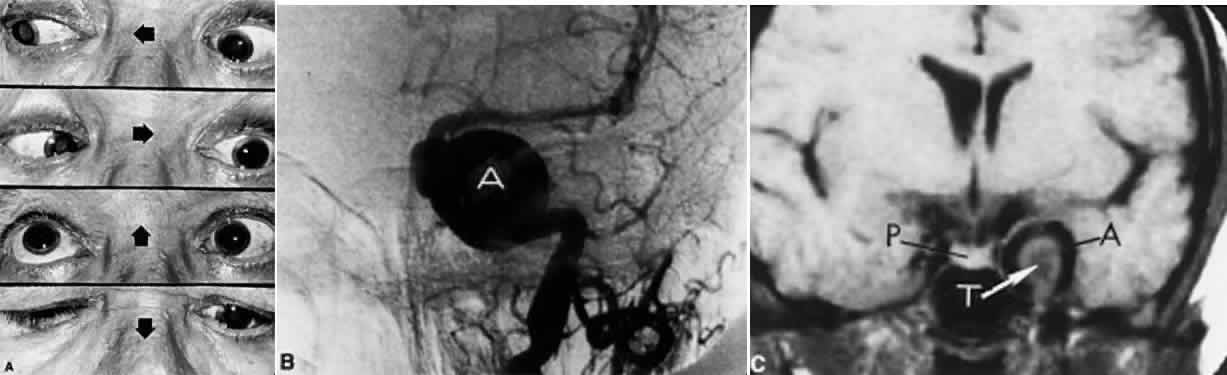

INTERPEDUNCULAR LESIONS

Basal lesions, including the rare rostral basilar artery aneurysm, may encroach on the oculomotor nerves as they exit in the interpeduncular space. Such slow-growing aneurysms, either saccular or fusiform, may present as partial oculomotor palsies with or without involvement of pyramidal tracts, and without subarachnoid hemorrhage.87 Aneurysms of the posterior communicating artery, on the other hand, are probably the most common lesions causing acute spontaneous oculomotor palsies (Fig. 12). According to Hyland and Barnett,88 the oculomotor palsy that occurs with posterior communicating aneurysm is not necessarily due to mass effect per se, but rather is attributed to hemorrhage that suddenly enlarges the aneurysmal sac to which the oculomotor nerve is adherent, or to hemorrhage into the substance of the nerve itself. Most patients present, therefore, with an intensely painful, complete unilateral oculomotor palsy in association with other signs and symptoms of subarachnoid hemorrhage. Few patients with symptomatic posterior communicating aneurysms are found in office waiting rooms: they are usually obtunded or comatose in emergency rooms.

Fig. 12. Sudden total right ophthalmoplegia accompanied by orbital pain, due to posterior communicating artery aneurysm. A. Complete right ptosis. B. Right eye in abducted position, with dilated pupil, fixed to light. C. Failure of adduction on left gaze. D. Right eye intorts (arrow) on downward gaze, indicating retained function of fourth nerve. E. Contrast-enhanced T-1 weighted MRI axial section shows aneurysm (arrows). Confirmed by angiography.

Involvement of pupillary fibers is such a consistent finding in third nerve palsies due to bleeding aneurysms that most clinicians concur in this useful dictum: a pupil-sparing, but otherwise complete, third nerve palsy is very unlikely to be due to posterior communicating aneurysms. Careful pupil evaluation may disclose subtle abnormalities in “apparent pupil-sparing,” especially in cases of aberrant regeneration or with chronic cavernous sinus lesions. Generally, in patients at least 50 years of age or older, an acute, isolated, painful oculomotor palsy that spares the pupil is caused by intraneural ischemia; nevertheless, these patients must be carefully observed for further evolution. In our opinion, an acute complete oculomotor palsy with moderate to major mydriasis, even when diabetes is present, is an indication for cerebral arteriography. It should be emphasized that magnetic resonance angiography may not detect aneurysms smaller than 3 to 4 mm.89